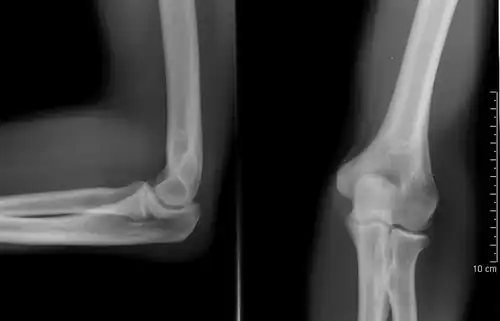

Normal radiograph; right picture of the straightened arm shows the carrying angle of the elbow

When the arm is extended, with the palm facing forward or up, the bones of the upper arm (humerus) and forearm (radius and ulna) are not perfectly aligned. The deviation from a straight line occurs in the direction of the thumb, and is referred to as the "carrying angle".[22]

The carrying angle permits the arm to be swung without contacting the hips. Women on average have smaller shoulders and wider hips than men, which tends to produce a larger carrying angle (i.e., larger deviation from a straight line than that in men). There is, however, extensive overlap in the carrying angle between individual men and women, and a sex-bias has not been consistently observed in scientific studies.[23]

The angle is greater in the dominant limb than the non-dominant limb of both sexes,[24] suggesting that natural forces acting on the elbow modify the carrying angle. Developmental,[25] aging and possibly racial influences add further to the variability of this parameter.